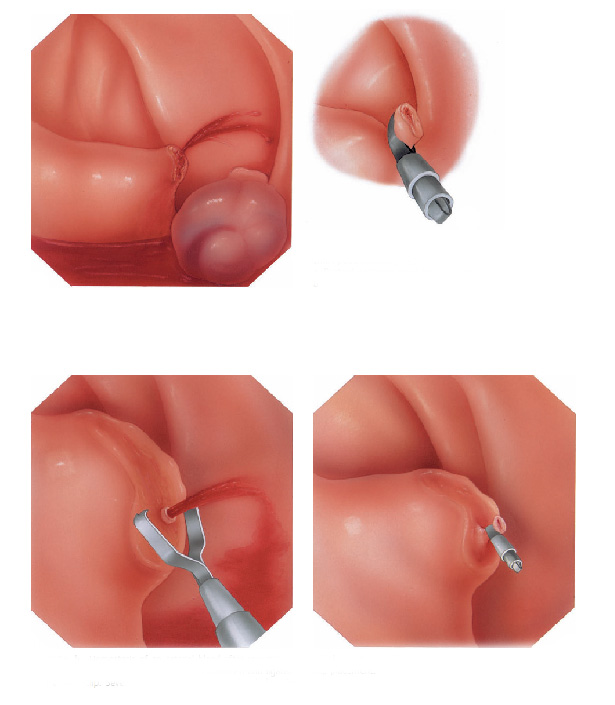

Mucosectomia é o procedimento realizado quando há necessidade de retirada de lesões maiores do trato gastrointestinal.

O exame de Mucosectomia é realizado através de injeção de liquido embaixo da lesão, através de uma agulha específica. Com isso a lesão se destaca das camadas mais profundas do intestino, diminuindo o risco de perfuração.

A retirada da lesão é feita com uma alça de polipectomia e o material é encaminhado para estudo anatomopatológico (no microscópio) da mesma forma que ocorre nas biópsias.

Polipectomia com pinça

Pequenos pólipos podem ser removidos com segurança usando-se apenas uma pinça.

Polipectomia com alça diatérmica

Pólipos maiores necessitam ser removidos com alça e corrente de cauterização. Este procedimento permite cortar a base do pólipo e ao mesmo tempo coagular o local para evitar sangramentos.

Porém alguns pólipos possuem a base (pedículo) largo onde passam vasos calibrosos e por isto tem risco aumentado de sangramento na retirada mesmo usando a corrente de coagulação.

Nestes casos algumas medidas podem ser realizadas para diminuir o risco de sangramento:

Injeção de adrenalina na base do pólipo

Colocação de um laço na base do pólipo para estrangular o pedículo

Alguns pólipos são tão grandes que não podem ser removidos inteiros. Nestes casos o pólipo é retirado em pedaços para poder garantir a sua remoção completa.

Alguns pólipos não possuem a base alongada (pedículo), estes são chamados de pólipos sésseis. A remoção destes pólipos possui risco maior de perfuração do órgão pois como são planos ficam muito próximos da parede externa do órgão.

Mucosectomia

Para diminuir este risco, injeta-se com um uma agulha uma solução abaixo do pólipo para que ele levante e fique mais longe da parede do órgão. Após isto passa-se a alça diatérmica e realiza-se o

procedimento de polipectomia.